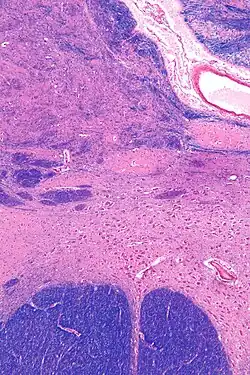

![]() Intermediate magnification micrograph of the nucleus basalis. LFB-HE stain. | |

The nucleus basalis in humans is a somewhat diffuse collection of large cholinergic neurons in the basal forebrain.[2] The main body of the nucleus basalis lies inferior to the anterior commissure and the globus pallidus, and lateral to the anterior hypothalamus in an area known as the substantia innominata.[1] Rostrally, the nucleus basalis is continuous with the cholinergic neurons of the nucleus of the diagonal band of Broca.[1] The nucleus basalis is thought to consist of several subdivisions based on the location of the cells and their projections to other brain regions.[2] Occasional neurons belonging to the nucleus basalis can be found in nearby locations such as the internal laminae of the globus pallidus and the genu of the internal capsule.[1]

NBM in relation to the globus pallidus and putamen - very low magnification. -